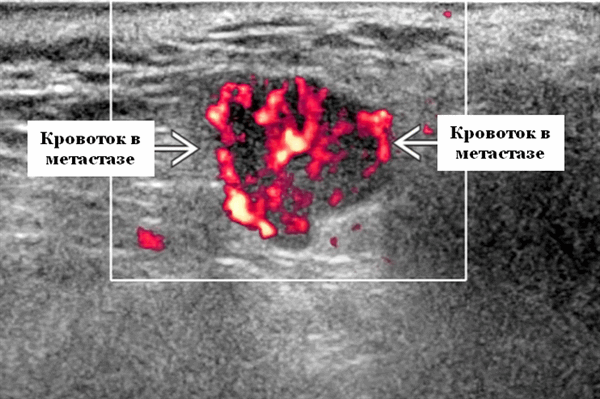

Энергетический допплер. Внутриочаговая васкуляризация. Хаотический / дезорганизованный или преимущественно периферический кровоток

Васкуляризация злокачественных опухолей не является патогномоничным при оценке цветового допплеровского картирования или энергетического допплера, поэтому УЗИ не дает достоверную дифференциацию между доброкачественными и злокачественными опухолями слюнных желез. Однако, есть предположение, что высокая васкуляризация и значительная пиковая систолическая скорость кровотока должны вызывать подозрение на злокачественность. При обследовании пациентов в Красноярске мы пришли к выводу, что опухоли, демонстрирующие увеличение индекса сосудистого сопротивления во внутриопухолевом кровотоке, имеют повышенный риск малигнизации. Наличие метастатического осложнения, сопровождающие опухоль слюнной железы, проявляется поражением лимфатических узлов, убедительно говорит о злокачественности.